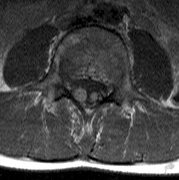

CNS hemangiomas are the most common tumor of VHL, affecting 60% to 80%, with a predilection for the cerebellum and spinal chord. An enlarging cystic component is a frequent finding in symptomatic tumors. Patients typically present in their early 30s; headaches or neck pain in affected individuals should not be ignored.172,173 On microscopy, CNS hemangiomas resemble retinal capillary hemangiomas. Their malignant potential is low.174 The treatment is surgical (Fig. 17, A and B).13

Fig. 17. Images from a 13-year-old boy with Von Hippel-Lindau syndrome. (a) Coronal postcontrast T1-weighted imaging reveals a cystic lesion with an enhancing nodule at the pial surface typical of a hemangioblastoma. (b) A second solid enhancing hemangioblastoma is seen at the craniocervial junction on a sagittal postcontrast T1-weighted image. (c) Associated cystic lesions (arrows) are seen within the pancreas.

PANCREAS.

Pancreatic lesions may be nonsecretory (most commonly cysts or cystadenomas) or secretory (islet cell tumor).179 In one study of 52 patients, 56% (29 patients) were found to have pancreatic lesions. The majority (19 of 29) had cystic changes only (Fig. 17C). Pancreatic lesions were the only abdominal manifestation of disease in 6 of 52 patients.180 In a separate study, pancreatic cysts did not show significant progression on follow-up examinations over an average period of 5 years.181 Like pancreatic cysts, islet cell tumors appear to be frequently asymptomatic.182